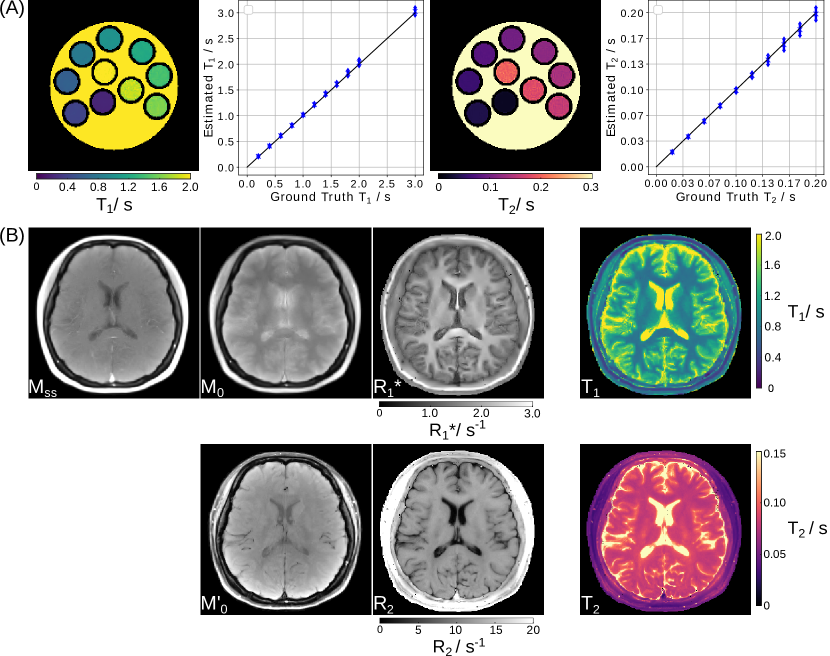

Refer to caption

Figure 3: Real-time liver images acquired during free-breathing using a radial multi-echo (ME) FLASH sequence. Model-based reconstruction directly and jointly estimates separated water and fat images, as well as R2superscriptsubscript𝑅2R_{2}^{\star} and B0subscript𝐵0B_{0} field maps.

where W and F are the water and fat magnetization, respectively. fpsubscript𝑓𝑝f_{p} is the p𝑝pth fat-spectrum peak frequency. In practice, usually the 6-peak fat spectrum [43] is used. In the model-based reconstruction formulation, the unknowns contain W, F, R2superscriptsubscript𝑅2R_{2}^{*}, and fB0subscript𝑓subscript𝐵0f_{B_{0}}, as well as a set of coil sensitivity maps from the parallel imaging model.

Here, a multi-echo (ME) radial FLASH sequence [31] was used to acquire liver data during free breathing. The model-based reconstruction was initialized by the estimate from model-based 3-point water/fat separation [31], while R2superscriptsubscript𝑅2R_{2}^{*} and coil sensitivity maps were initialized with 0. Afterwards, joint estimation of all unknowns in Equation (7) including coil sensitivity maps was achieved via IRGNM with ADMM. The Sobolev-norm weight [41] was applied to the B0subscript𝐵0B_{0} field inhomogeneity and coil sensitivity maps. Joint 11\ell 1-Wavelet regularization was applied to other parameter maps. As shown in Figure 3 and Supplementary Video 3, high-quality respiratory-resolved water/fat separation as well as R2superscriptsubscript𝑅2R_{2}^{*} and fB0subscript𝑓subscript𝐵0f_{B_{0}} maps can be achieved even with undersampled multi-echo radial acquisition (33 spokes per echo and 7 echoes in total).